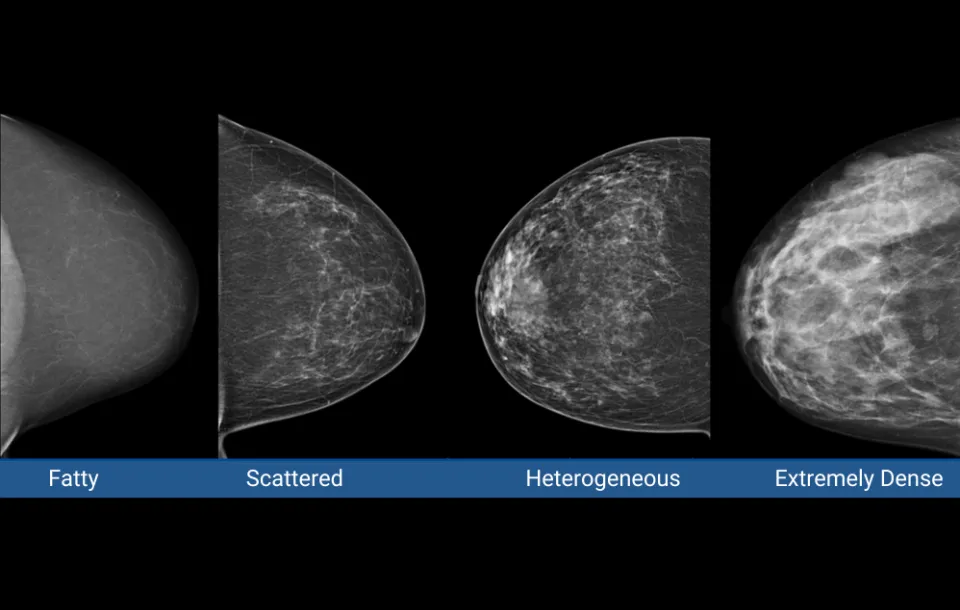

- Understand the structure and function of the breast, focusing on the factors that contribute to dense breast tissue

- Explore the latest mammography machines equipped with breast density software

- Learn about computer software that assists radiologists in selecting breast density categories